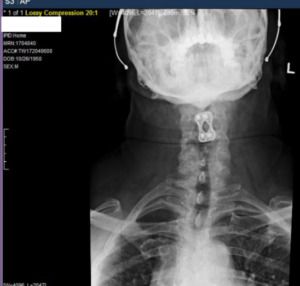

The outcome can be even worse when damage occurs to the spinal cord – a bundle of nerves that run through the neck and backbones called vertebrae. The spinal cord allows the brain to communicate with the rest of the body. Damage to the spinal cord itself can cause paralysis.